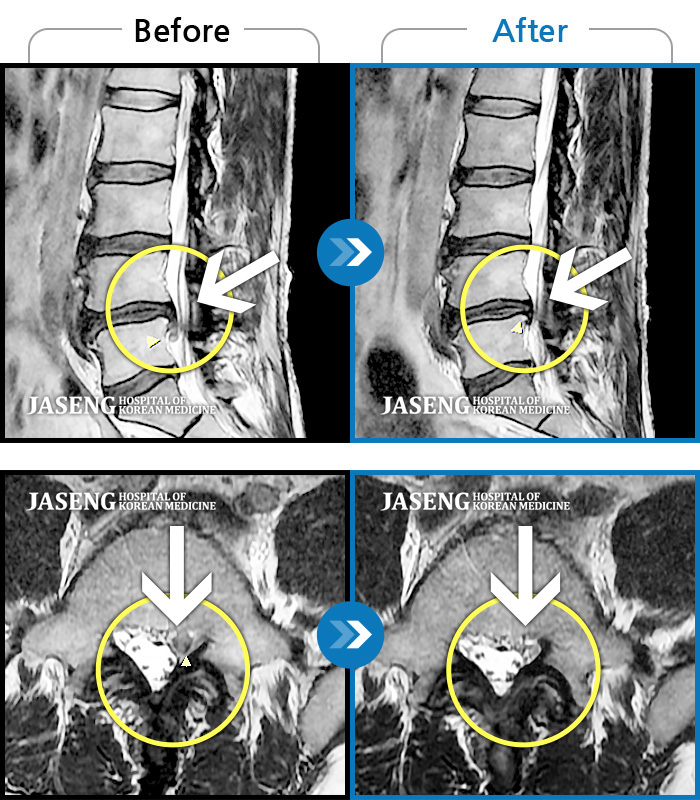

허리협착증으로 입원치료했는데 너무 친절하게 설명도 잘 하시고 치료도 잘 해주셔서 덕분에 오늘 퇴원합니다 원재균원장님 감사합니다~^^

아내가 무릎관절과 척추협착증세로 근 20여년 고생을~! 병원에선 수술권유에 걱정하든중, 수술않고 노후를 갈망하던중 오직 자생한방 병원의 신바로치료(일명 약침) 를 원재균 원장님께서 친가족처럼 친절과 따뜻한 치료를받고 있으며, 아내는 엄청호전으로 대만족 으로 노후를 잘 보낼수있게됐다고 원재균원장님께 감사의 마음을 전합니다. 남편으로서 정말 고맙고 감사합니다! 원재균원장님 !! 자생한방 신바로치료 선택을 정말한것 같습니다! 항시 가족처럼 치료를 잘 해주시는 원장님께 감사와 고마움을 드립니다 !! 원장님~!!!

평소 혈압으로 10년이상 등산, 헬스등 운동을 꾸준히 해오며 양측무릎과 허리통증이 심해 정형외과에서 무릎 퇴행성 관절염, 척추 협착증으로 진단 받았습니다 특히 계단 내려올때 내리막길 통증이 심하며 허리는 서있을경우 통증이 많이 올라옵니다 정형외과에서 수술권유해서 주변지인들로 수술 휴유증으로 약을 복용해도 통증이 잡히지않고 오히려 더 아픈 경우를 봐서 수술 않고 치료 할수 있는 병원을 찾다 지인 소개로 원재균 원장님을 뵙게 되었습니다 선한인상과 친절한 모습과 말투에서 우선 마음이 편안한 느낌 이었습니다 최대한 환자를 배려하는 행동이 몸에 배였다고 할까요 ㅎ 일반 정형외과나 병원에서는 볼수없는 모습에 깜짝 놀랄 정도 였습니다 정형외과에서 찍은 자료를 보시고 수술 안하고도 한방으로 약침, 침, 부항, 한약으로 치료받아 통증이 줄어들고, 일상생활이 가능할수 있다고 말씀 하셨습니다 관절이라 사용할수 있을때까지 사용하는게 좋다는게 저의 생각과 같았습니다 수술을 너무 싫어하는 저에겐 정말 도전해 볼만 했습니다 원장님을 믿고 치료한지 이제 한달이 다되어가는데 이제는 정형외과 약 안먹고도 극심한 통증없이 비오는 날만 한번씩 통증이 있는 정도 입니다 매번 내원시 그동안 어떻게 지내셨는지 통증이 어땠는지 세심하게 챙기시며 저를 살뜰히 봐주시는게 마음이 따뜻하게 느껴지고 치료받고 나면 좋아지는 느낌입니다 실력도 좋고, 마음도 따뜻한 원재균 원장님 감사의 표현을 꼭 하고싶었습니다" 진심으로 감사합니다 "